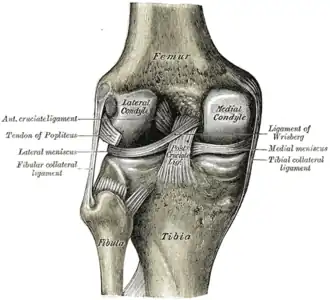

Ligaments

The ligaments surrounding the knee joint offer stability by limiting movements and, together with the menisci and several bursae, protect the articular capsule.[19]

Intracapsular

The knee is stabilized by a pair of cruciate ligaments. These ligaments are both extrasynovial, intracapsular ligaments.[20] The anterior cruciate ligament (ACL) stretches from the lateral condyle of femur to the anterior intercondylar area.[13] The ACL prevents the tibia from being pushed too far anterior relative to the femur.[13] It is often torn during twisting or bending of the knee.[21] The posterior cruciate ligament (PCL) stretches from medial condyle of femur to the posterior intercondylar area. This ligament prevents posterior displacement of the tibia relative to the femur.[13] Injury to this ligament is uncommon but can occur as a direct result of forced trauma to the ligament.

The transverse ligament stretches from the lateral meniscus to the medial meniscus. It passes in front of the menisci. It is divided into several strips in 10% of cases.[10]: 208 The two menisci are attached to each other anteriorly by the ligament.[22] The posterior (of Wrisberg) and anterior meniscofemoral ligaments (of Humphrey) stretch from the posterior horn of the lateral meniscus to the medial femoral condyle. They pass anterior and posterior to the posterior cruciate ligament respectively.[13][10]: 208 The meniscotibial ligaments (or "coronary") stretches from inferior edges of the menisci to the periphery of the tibial plateaus.

Extracapsular

The patellar ligament connects the patella to the tuberosity of the tibia. It is also occasionally called the patellar tendon because there is no definite separation between the quadriceps tendon (which surrounds the patella) and the area connecting the patella to the tibia.[23] This very strong ligament helps give the patella its mechanical leverage[24] and also functions as a cap for the condyles of the femur. Laterally and medially to the patellar ligament, the lateral and medial retinacula connect fibers from the vasti lateralis and medialis muscles to the tibia. Some fibers from the iliotibial tract radiate into the lateral retinaculum and the medial retinaculum receives some transverse fibers arising on the medial femoral epicondyle.[10]: 206

The medial collateral ligament (MCL a.k.a. "tibial") stretches from the medial epicondyle of the femur to the medial tibial condyle. It is composed of three groups of fibers, one stretching between the two bones, and two fused with the medial meniscus. The MCL is partly covered by the pes anserinus and the tendon of the semimembranosus passes under it.[10]: 206 It protects the medial side of the knee from being bent open by a stress applied to the lateral side of the knee (a valgus force).[10]: 206

The lateral collateral ligament (LCL a.k.a. "fibular") stretches from the lateral epicondyle of the femur to the head of fibula. It is separate from both the joint capsule and the lateral meniscus.[10]: 206 It protects the lateral side from an inside bending force (a varus force). The anterolateral ligament (ALL) is situated in front of the LCL.

Lastly, there are two ligaments on the dorsal side of the knee. The oblique popliteal ligament is a radiation of the tendon of the semimembranosus on the medial side, from where it is direct laterally and proximally. The arcuate popliteal ligament originates on the apex of the head of the fibula to stretch proximally, crosses the tendon of the popliteus muscle, and passes into the capsule.[10]: 206

Illustrations

-

Cruciate ligaments -

Left knee-joint from behind, showing interior ligaments. -

Capsule of right knee-joint (distended). Lateral aspect. -

Anterior and lateral view of knee. -

Anterior view of knee.